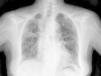

Caso clínicoSe trata de una mujer de 83 años, con antecedentes de hipertensión arterial en tratamiento con amlodipino 5mg/día, enfermedad renal crónica en estadio iii, secundario a nefroangioesclerosis (filtrado glomerular de 45ml/min) y polimialgia reumática en tratamiento crónico con metotrexato 15mg/semanal, desde hace 4 años, aproximadamente. Durante los últimos años ha permanecido con buena estabilidad clínica y analítica, no requiriendo tratamiento corticoideo asociado ni ajustes de su medicación habitual. Seis semanas previas al ingreso presentó de forma progresiva astenia, disnea, tos productiva y pérdida ponderal de 5 kg durante este tiempo. No fiebre termometrada, no artralgias ni debilidad muscular. En el ingreso, se objetivó disnea en reposo con saturación de oxigeno basal del 90%, auscultación pulmonar con crepitantes finos bilaterales, no adenomegalias ni visceromegalias palpables, elevación de la velocidad de sedimentación globular de 69mm, proteína C reactiva de 3,5mg/dl y radiografía de tórax, donde destacó un infiltrado reticular bilateral difuso y asimétrico con afectación periférica, más acentuado en las bases y en el lóbulo superior derecho (fig. 1). Tras realizar un diagnóstico diferencial de neumopatía subaguda en el contexto de la paciente, la sospecha de neumopatía por metotrexato fue el principal planteamiento, por lo que se suspendió dicho tratamiento, se inició corticoterapia por vía intravenosa de 48mg/día de metilprednisolona y medidas de soporte, a pesar de lo cual no se objetivó clara mejoría. Se realizó una tomografía axial computarizada de alta resolución (TACAR) torácico, objetivándose un engrosamiento intersticial parcheado de predominio periférico y en las bases pulmonares, así como pequeñas adenopatías mediastínicas inespecíficas (fig. 2). Las pruebas de función respiratoria mostraron una espirometría forzada con valores en el límite bajo de la normalidad, con una capacidad vital forzada (FVC) de 1.340ml (82%), un volumen de flujo espiratorio en el primer segundo (FEV1) de 1.130ml (88%) y el cociente FEV1/FVC del 84%, asociado a un descenso grave de la difusión pulmonar de monóxido de carbono (DLCO) del 33% y corregido según el volumen alveolar (KCO) del 54%. En el resto de las pruebas complementarias, no se evidenciaron alteraciones en el hemograma, la serología para gérmenes atípicos, el estudio de marcadores tumorales, los hemocultivos, el estudio seriado de esputo ni en el Mantoux/Booster, por lo que se realizó una broncoscopia con estudio del lavado broncoalveolar (LBA) y broncoaspirado, obteniéndose resultado positivo en la reacción en cadena de la polimerasa (PCR) para CMV asociado a un incremento del índice de linfocitos CD4/CD8 de 3.47, con el resto de estudio para gérmenes comunes, tuberculosis, Pneumocistis jiroveci y hongos negativo. Se amplió el estudio microbiológico detectándose IgG para CMV (+), IgM para CMV (–) y carga viral CMV en plasma (+), por lo que se inició tratamiento por vía intravenoso, ajustado según función renal, con ganciclovir 300mg/12 h durante 14 días, cambiando posteriormente a valganciclovir 900mg/12 h por vía oral durante 14 días, con buena tolerancia a la medicación y respuesta clínica, mejorando los parámetros radiológicos, serológicos (carga viral CMV indetectable) y de función respiratoria (DLCO 57,52%, KCO 80,90%, FVC 1.950ml [119%] y FEV1 de 1.680ml [130%]).